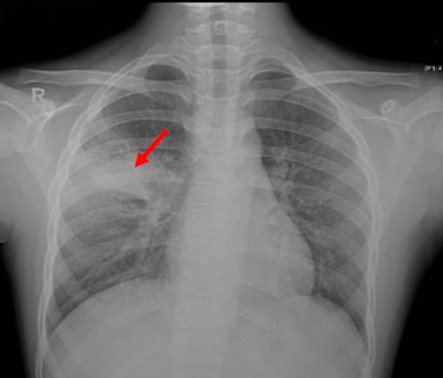

Paciente masculino de 23 años quien es llevado a consulta por productiva, malestar general fatiga y

disnea. Menciona además que últimamente ha tenido que utilizar más veces al día

su tratamiento de rescate para asma. Entre los antecedentes menciona que cree

que la Pachamama es perfecta, así que se come todas las verduras tal cual las

recoge de la siembra sin lavarla ni hervirla. Además, menciona tener malestar

abdominal, dolores tipo cólico, náuseas, meteorismo, vómitos ocasionales y

diarrea. Se le realiza un examen de heces que menciona que tiene

"huevos" y una biopsia pulmonar que verán a continuación... Con base

a toda la información... ¿Cuál de las siguientes radiografías torácicas es más

probable que tenga este paciente?